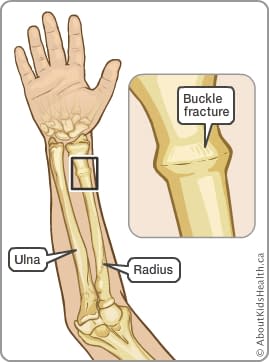

This is usually not torn and holds the bones in place. In addition, the layer of soft tissue over the bone, called the periosteum (which means the "tissue around the bone"), is quite thick and strong. When the bones of a child are stressed more than they can tolerate, they can buckle (which means bend) or deform like a green stick. The bones of children are still growing and are not as brittle as the bones of adults. This fracture is called a buckle fracture or a greenstick fracture. The large bone on the left is called the radius, the other bone is called the ulna. This is a close-up view of the wrist area. There is only a small bending of the cortex (outer part) of the bone. Surgical repair of pediatric hand and wrist fractures is rarely required in situations where the bone cannot be set straight or if it not healing properly with cast treatment.The fracture is indicated by the red arrows. Sometime the fracture will need to be “set” straight before splinting. Delayed treatment of pediatric fractures can lead to undesirable outcomes including malunion (bone doesn’t heal straight), and nonunion (bone doesn’t heal at all).Īnd casting are the mainstays of nonoperative treatment for fractures that are stable and not badly displaced (out of alignment). Even without these warning signs, it is best to seek urgent treatment so that the fracture can be set straight and Or “tight” swelling, significant deformity, or any open wounds around the hand or wrist (possible open or compound fracture). Suspected hand and wrist fractures warrant emergent treatment if your child is experiencing hand numbness and tingling, severe Yes! Some fractures are obvious if there is a deformity, but typically X-ray is used to definitively diagnose the fracture and plan treatment. Is There a Test for Hand and Wrist Fractures?